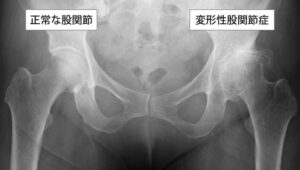

アイキャッチ画像:筋肉の代弁者早いものでもう2月。右股…